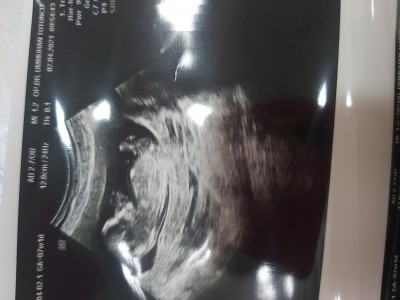

image112 haftalik doktor tahminde bulundu ama tam net değil dedi sizce

Kız bu kız :D

Erkek bence öle hissettim sadecs

Benim oğlumun ultrasonuyla benziyor ama hiç anlamam kuzum Allah gönlündekini nasip etsin

Sanki ikiz gebelik

erkege benzettim canm hayırlısı olsun hakkında :)

Erkek geçti içimden

Kız geçti icimden.

Kiz canım hayırlı olsun